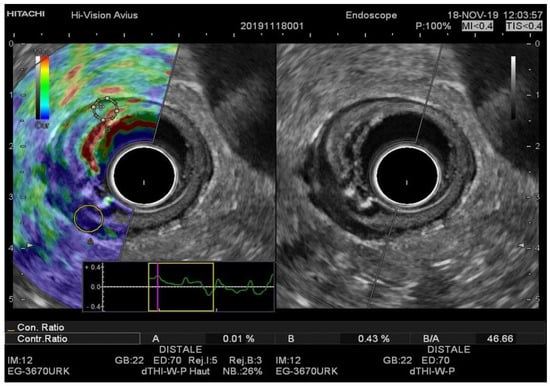

Figure 2. (A) EUS-RTE aspect in a 59-year-old male with pT2 rectal cancer. The tumor was classified as T2 by using the strain ratio (B/A); (B) EUS aspect of the same tumor confirmed by histopathologic examination after surgical resection. RTE, real-time elastography; EUS, flexible endorectal ultrasound.

Figure 3. (A) EUS-RTE aspect in a 67-year-old female with pT3 rectal cancer. (B) EUS aspect of the same tumor. The tumor was classified as T3 with the cutoff value strain ratio (B/A) of 46.66. T3 was confirmed by histopathologic examination after surgical resection. RTE, real-time elastography.